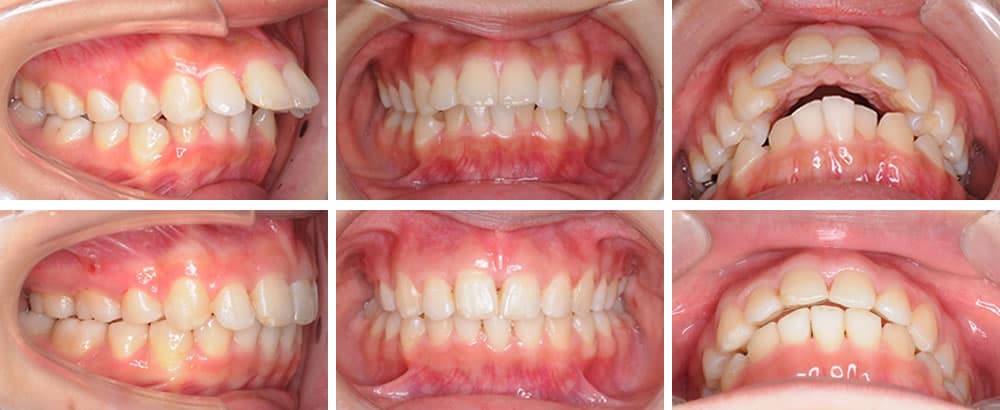

叢生(八重歯など)

叢生は歯が様々な向きに生え、ばらばらな状態の歯並びです。歯が重なった部分のケアが難しいため、虫歯や歯周病リスクが高くなります。また、見た目も悪くコンプレックスに感じる方も少なくありません。

上顎前突(出っ歯)

上顎前突は上の顎や歯が前方に出ている状態の歯並びです。口腔内が乾燥しやすいため、唾液の殺菌作用が低下し、虫歯や歯周病リスクが高くなります。また、見た目が悪いことや前歯を損傷しやすいことも特徴です。

下顎前突(受け口)

下顎前突は下の顎や歯が前方に出ている状態の歯並びです。前歯の咬み合わせが悪く、奥歯の使用頻度が高くなるため、奥歯の喪失リスクが高くなります。また、顎骨にも負担がかかるため、顎関節症になりやすいという特徴があります。

開咬(オープンバイト)

開咬は上下の歯を咬み合わせた際、前歯が咬み合わずに隙間ができてしまう歯並びです。正しい咀嚼ができないため、胃腸などの消化器官に負担がかかります。また、口腔内が乾燥しやすく、唾液の殺菌作用が低下するため、虫歯・歯周病リスクが高くなります。

過蓋咬合(ディープバイト)

過蓋咬合は上下の歯を咬み合わせた際、下の歯が見えなくなるほど上の歯の咬み合わせが深い歯並びです。下の歯で上の歯茎を傷つけたり、正しい咀嚼ができないことで顎骨や胃腸に大きな負担がかかったりなど、様々な問題が懸念されます。

空隙歯列(すきっ歯)

空隙歯列は歯と歯の間が大きく開いた状態の歯並びです。食べ物が挟まりやすいため、虫歯や歯周病リスクが高くなります。また、見た目の問題や歯の間から空気が抜けることによる発音障害などが懸念されます。